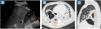

A 41-year-old male patient was admitted following a hypoxic cardiac arrest with a tooth aspiration in the right lower lobe, which was removed using a rigid bronchoscope. Despite appropriate antibiotic treatment for pneumonia, the patient developed a sepsis. Point-of-care ultrasound (POCUS) revealed a lung abscess (LA) associated to a pleural empyema (PE). On parasagittal section (Fig. 1 A), lung ultrasound showed a right lower lobe abscess appearing as a rounded anechoic image above the diaphragm, with suspended microbubbles (air content). Condensed lung parenchyma (CL) was observed around the structure. Behind it was another collection with smooth margins, a lenticular wall attached to the pleura, which appeared to be pleural empyema. The association of a LA with PE suggested the existence of bronchopleural fistula. A subsequent chest computed tomography scan confirmed this diagnosis, with transverse (B) and parasagittal (C) sections (Fig. 1).